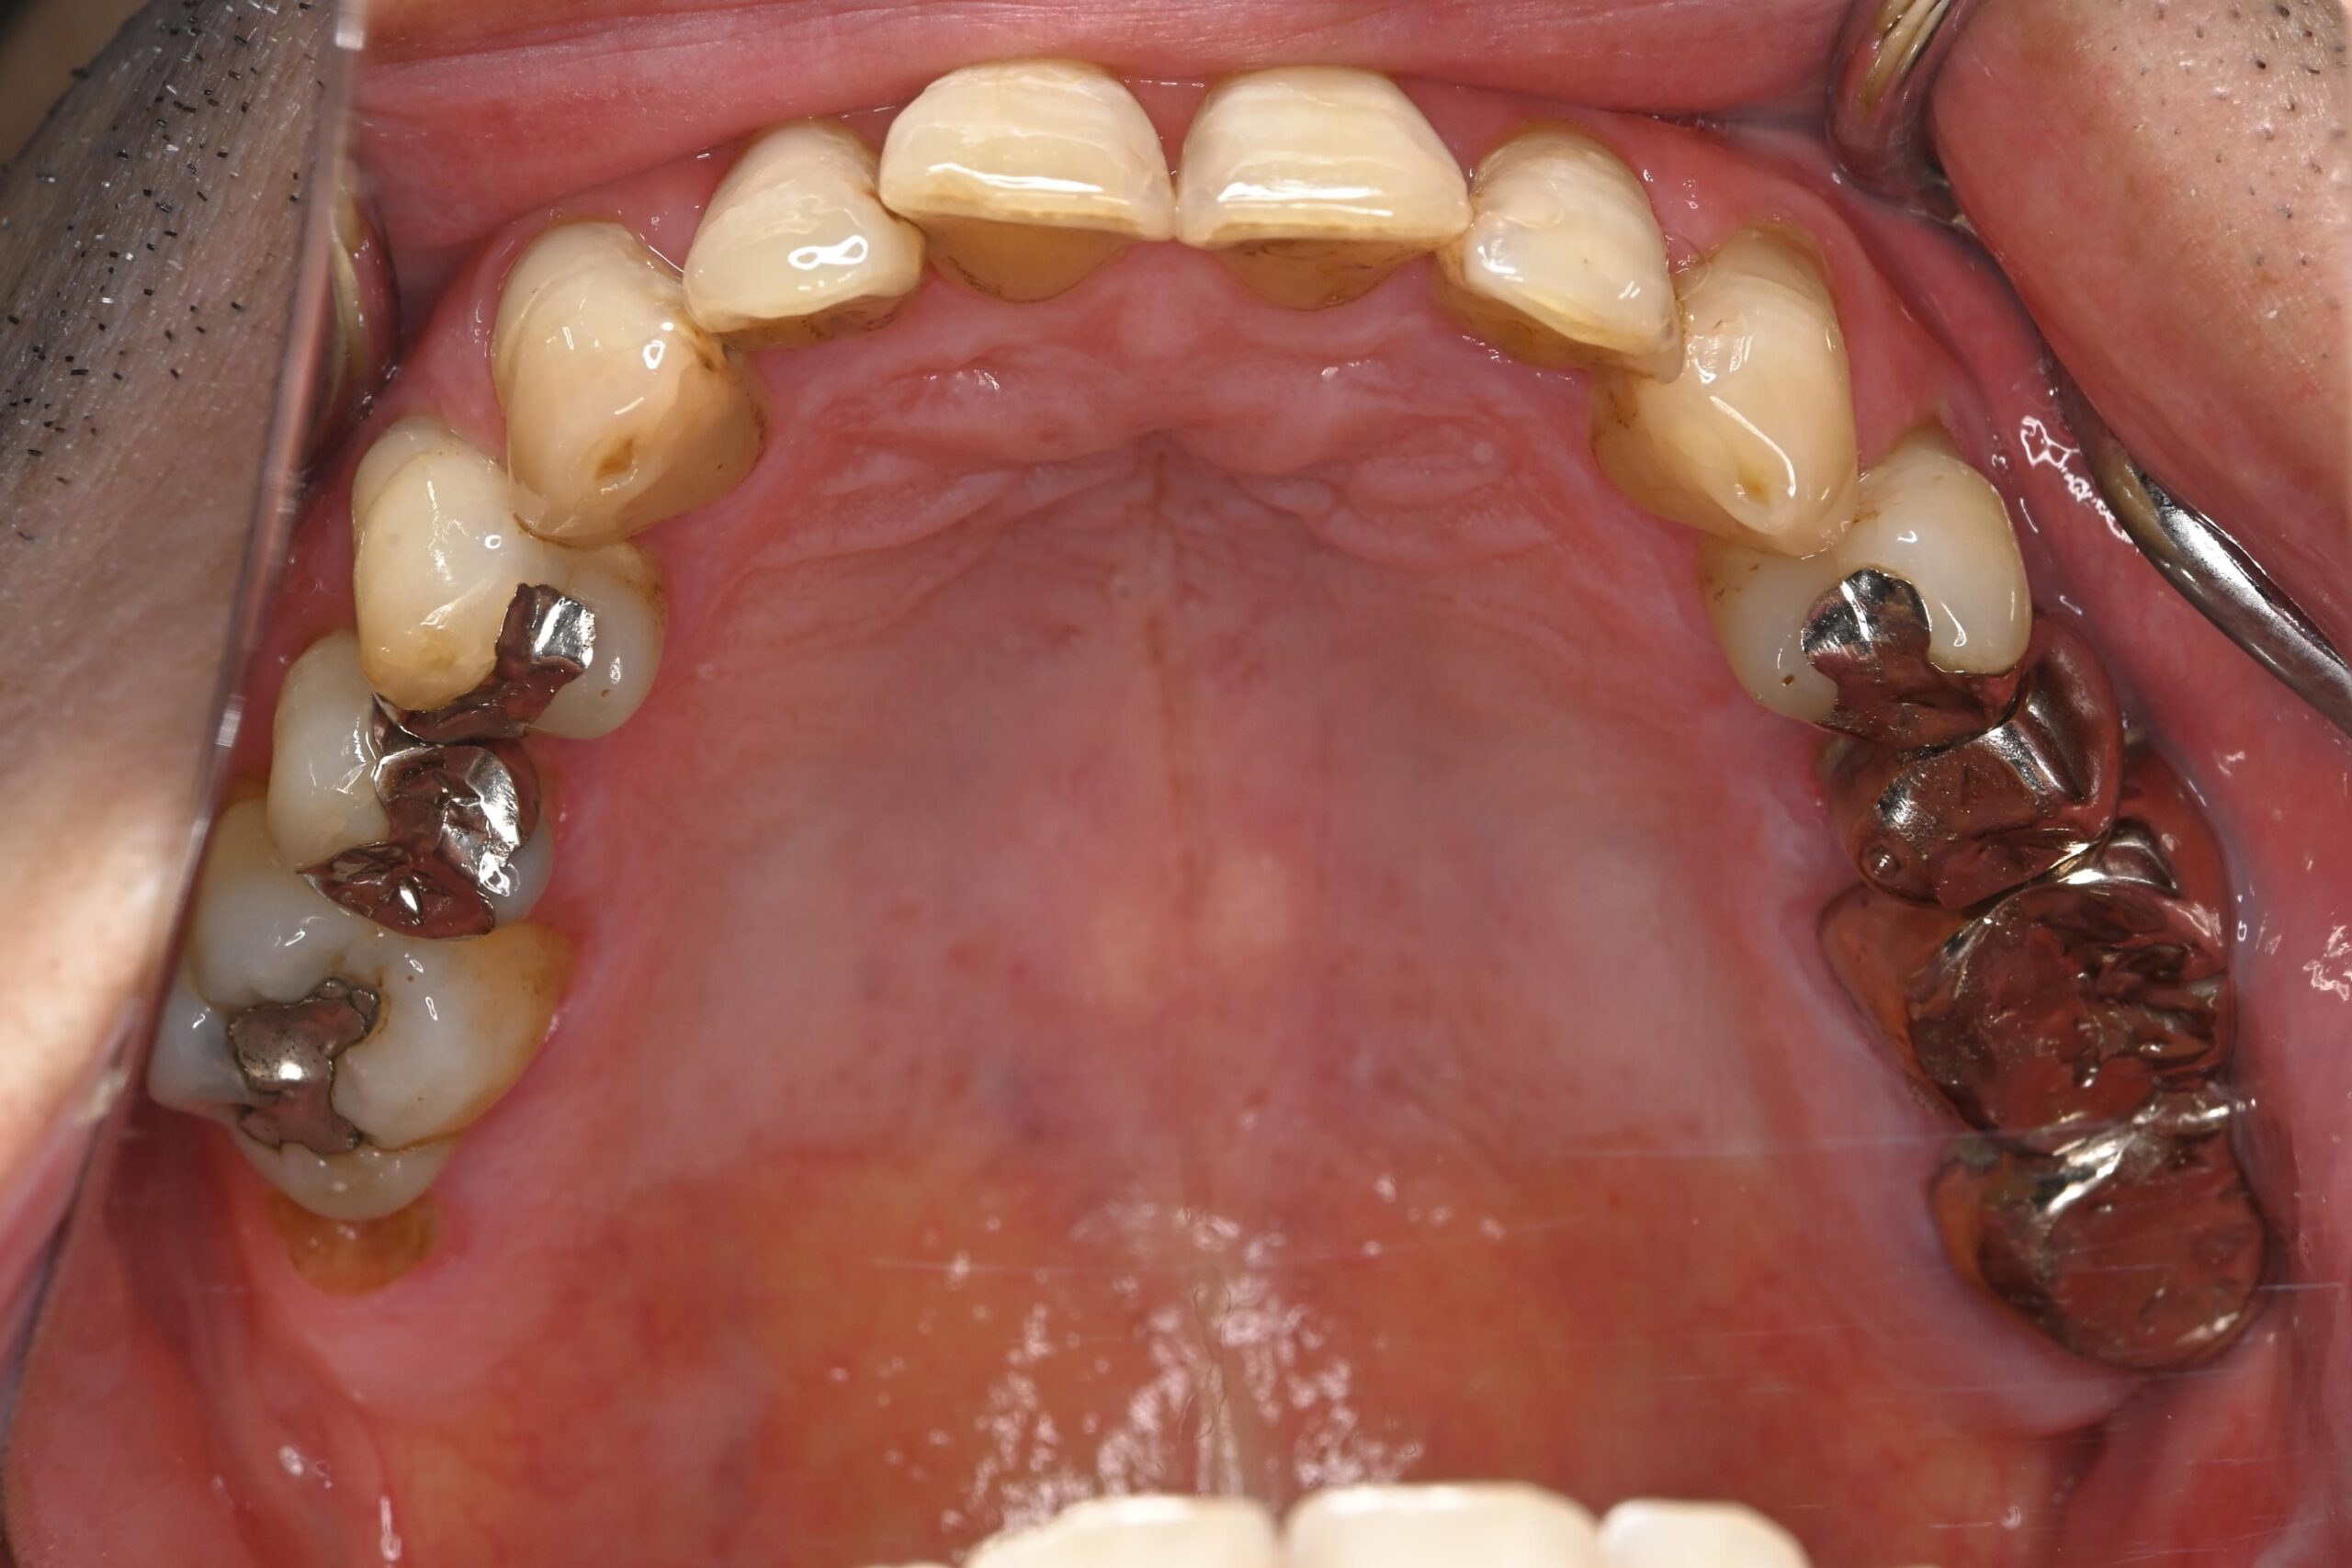

初診時の口腔内の状態:

お口全体に虫歯や歯周病の原因となるプラーク(歯垢)が多く付着していました。右上奥歯は重度の虫歯で歯冠部(歯の頭)が失われており、左下奥歯は過去の治療箇所から細菌が入り込み、根の先に炎症が起きている状態でした。

患者様と相談の結果、期間や費用の面から矯正治療は行わず、「現在の噛み合わせを整えながら、金属をセラミックへやり替える治療」を選択しました。

セラミックを作製する前に全体的なトーンアップを行い、基準となる色を作りました。 - 審美修復(セラミック治療):

前歯の虫歯治療と、奥歯の古い金属をセラミックへ交換しました。 - 噛み合わせの調整:

切端咬合による噛み合わせの負担を考慮し、補綴材料としてジルコニアを選択しました。

ジルコニアは非常に高い強度と耐久性を持つ素材で、強い咬合力がかかる症例においても破折リスクを抑えやすい特性があります。 - 「色」へのこだわり:

Before